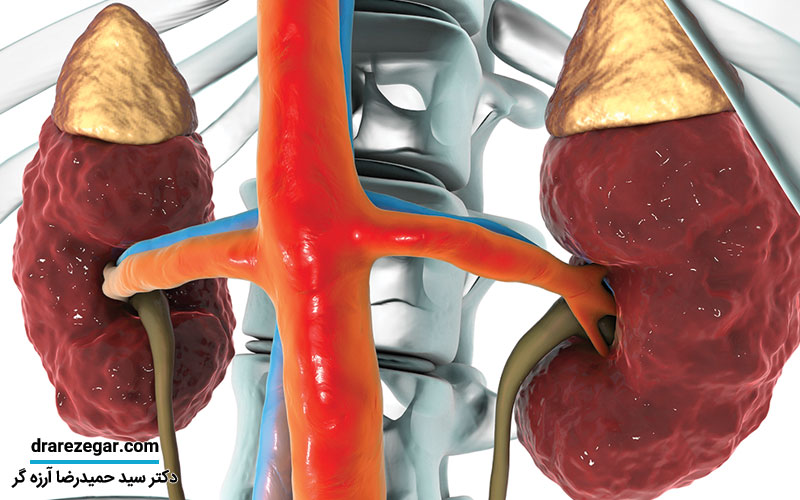

کلیه در بدن دو عضو کوچک لوبیا شکل است که در دو طرف ستون مهره ها و کمی پایین تر از قفسه سینه جای گرفته است. این دو عضو حیاتی وظایف بسیار مهمی مثل دفع مواد زائد و مایعات اضافی از بدن، تنظیم فشار خون و تصفیه خون را برعهده دارد. هرگونه مشکل در این دو کلیه می تواند عوارض جبران ناپذیری را به همراه داشته باشد. بسیاری از مواقع شما بدون آن که متوجه شوید، کلیه هایتان دچار مشکل می شود و در نتیجه این مشکل با علائمی مثل خستگی، نیاز به دفع ادرار به صورت مکرر و بی اشتهایی بروز می کند. اگر علایم اختلال عملکرد کلیه را بشناسید خیلی زود و به موقع می توانید مشکلات بدن خود را تشخیص دهید و از سلامت اعضای حیاتی به خصوص کلیه آگاه باشید. اگر می خواهید بدانید که آیا کلیه های شما سالم است یا نه این مقاله از مجموعه مقالات سایت دکتر سید حمیدرضا آرزه گر را به هیچ عنوان از دست ندهید.

دو عضو لوبیایی شکل که در طرفین مهره های ۱ تا ۴ کمری و قسمت پشت شکم قرار دارند وظیفه دفع سموم و مواد زائد بدن را برعهده خواهند داشت. این دو کلیه می توانند خون را به طور کل تصفیه و پاکسازی کنند. سایز کلیه ها به اندازه یک مشت بسته بوده و وزن آن ها حدوداً ۱۵۰ گرم گزارش شده است. لازم به ذکر است که کلیه ها می توانند تعادل آب و الکترولیت بدن را تنظیم کنند و همچنین فشار خون را کنترل کرده و وظایف حیاتی دیگری مثل سنتز و ساخت گلبول قرمز و ویتامین D را نیز انجام دهند. به طور کلی می توان عملکرد کلیه را در موارد زیر خلاصه کرد: